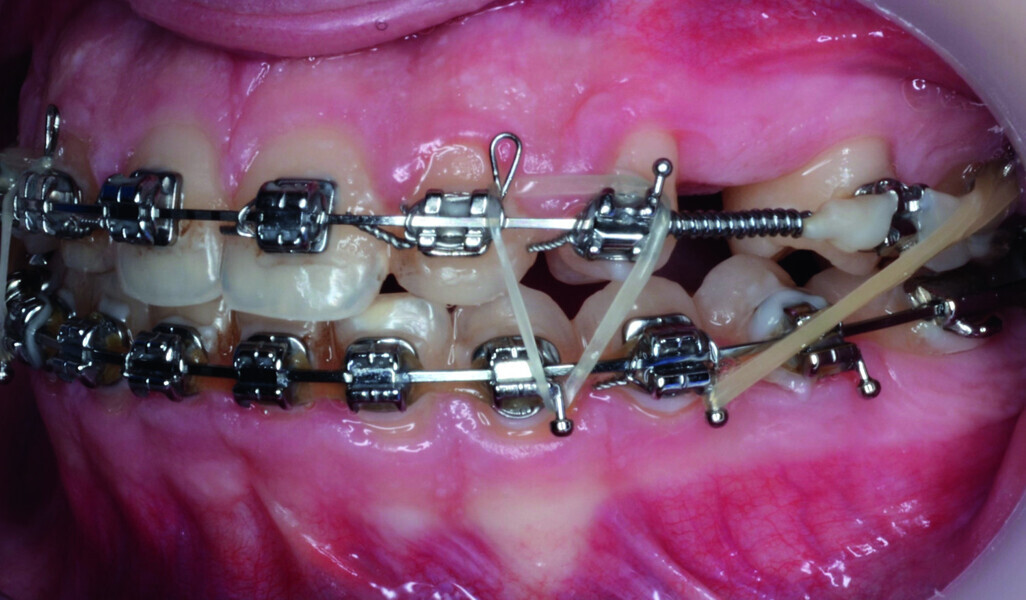

Orthodontic management of maxillary lateral incisors agenesis